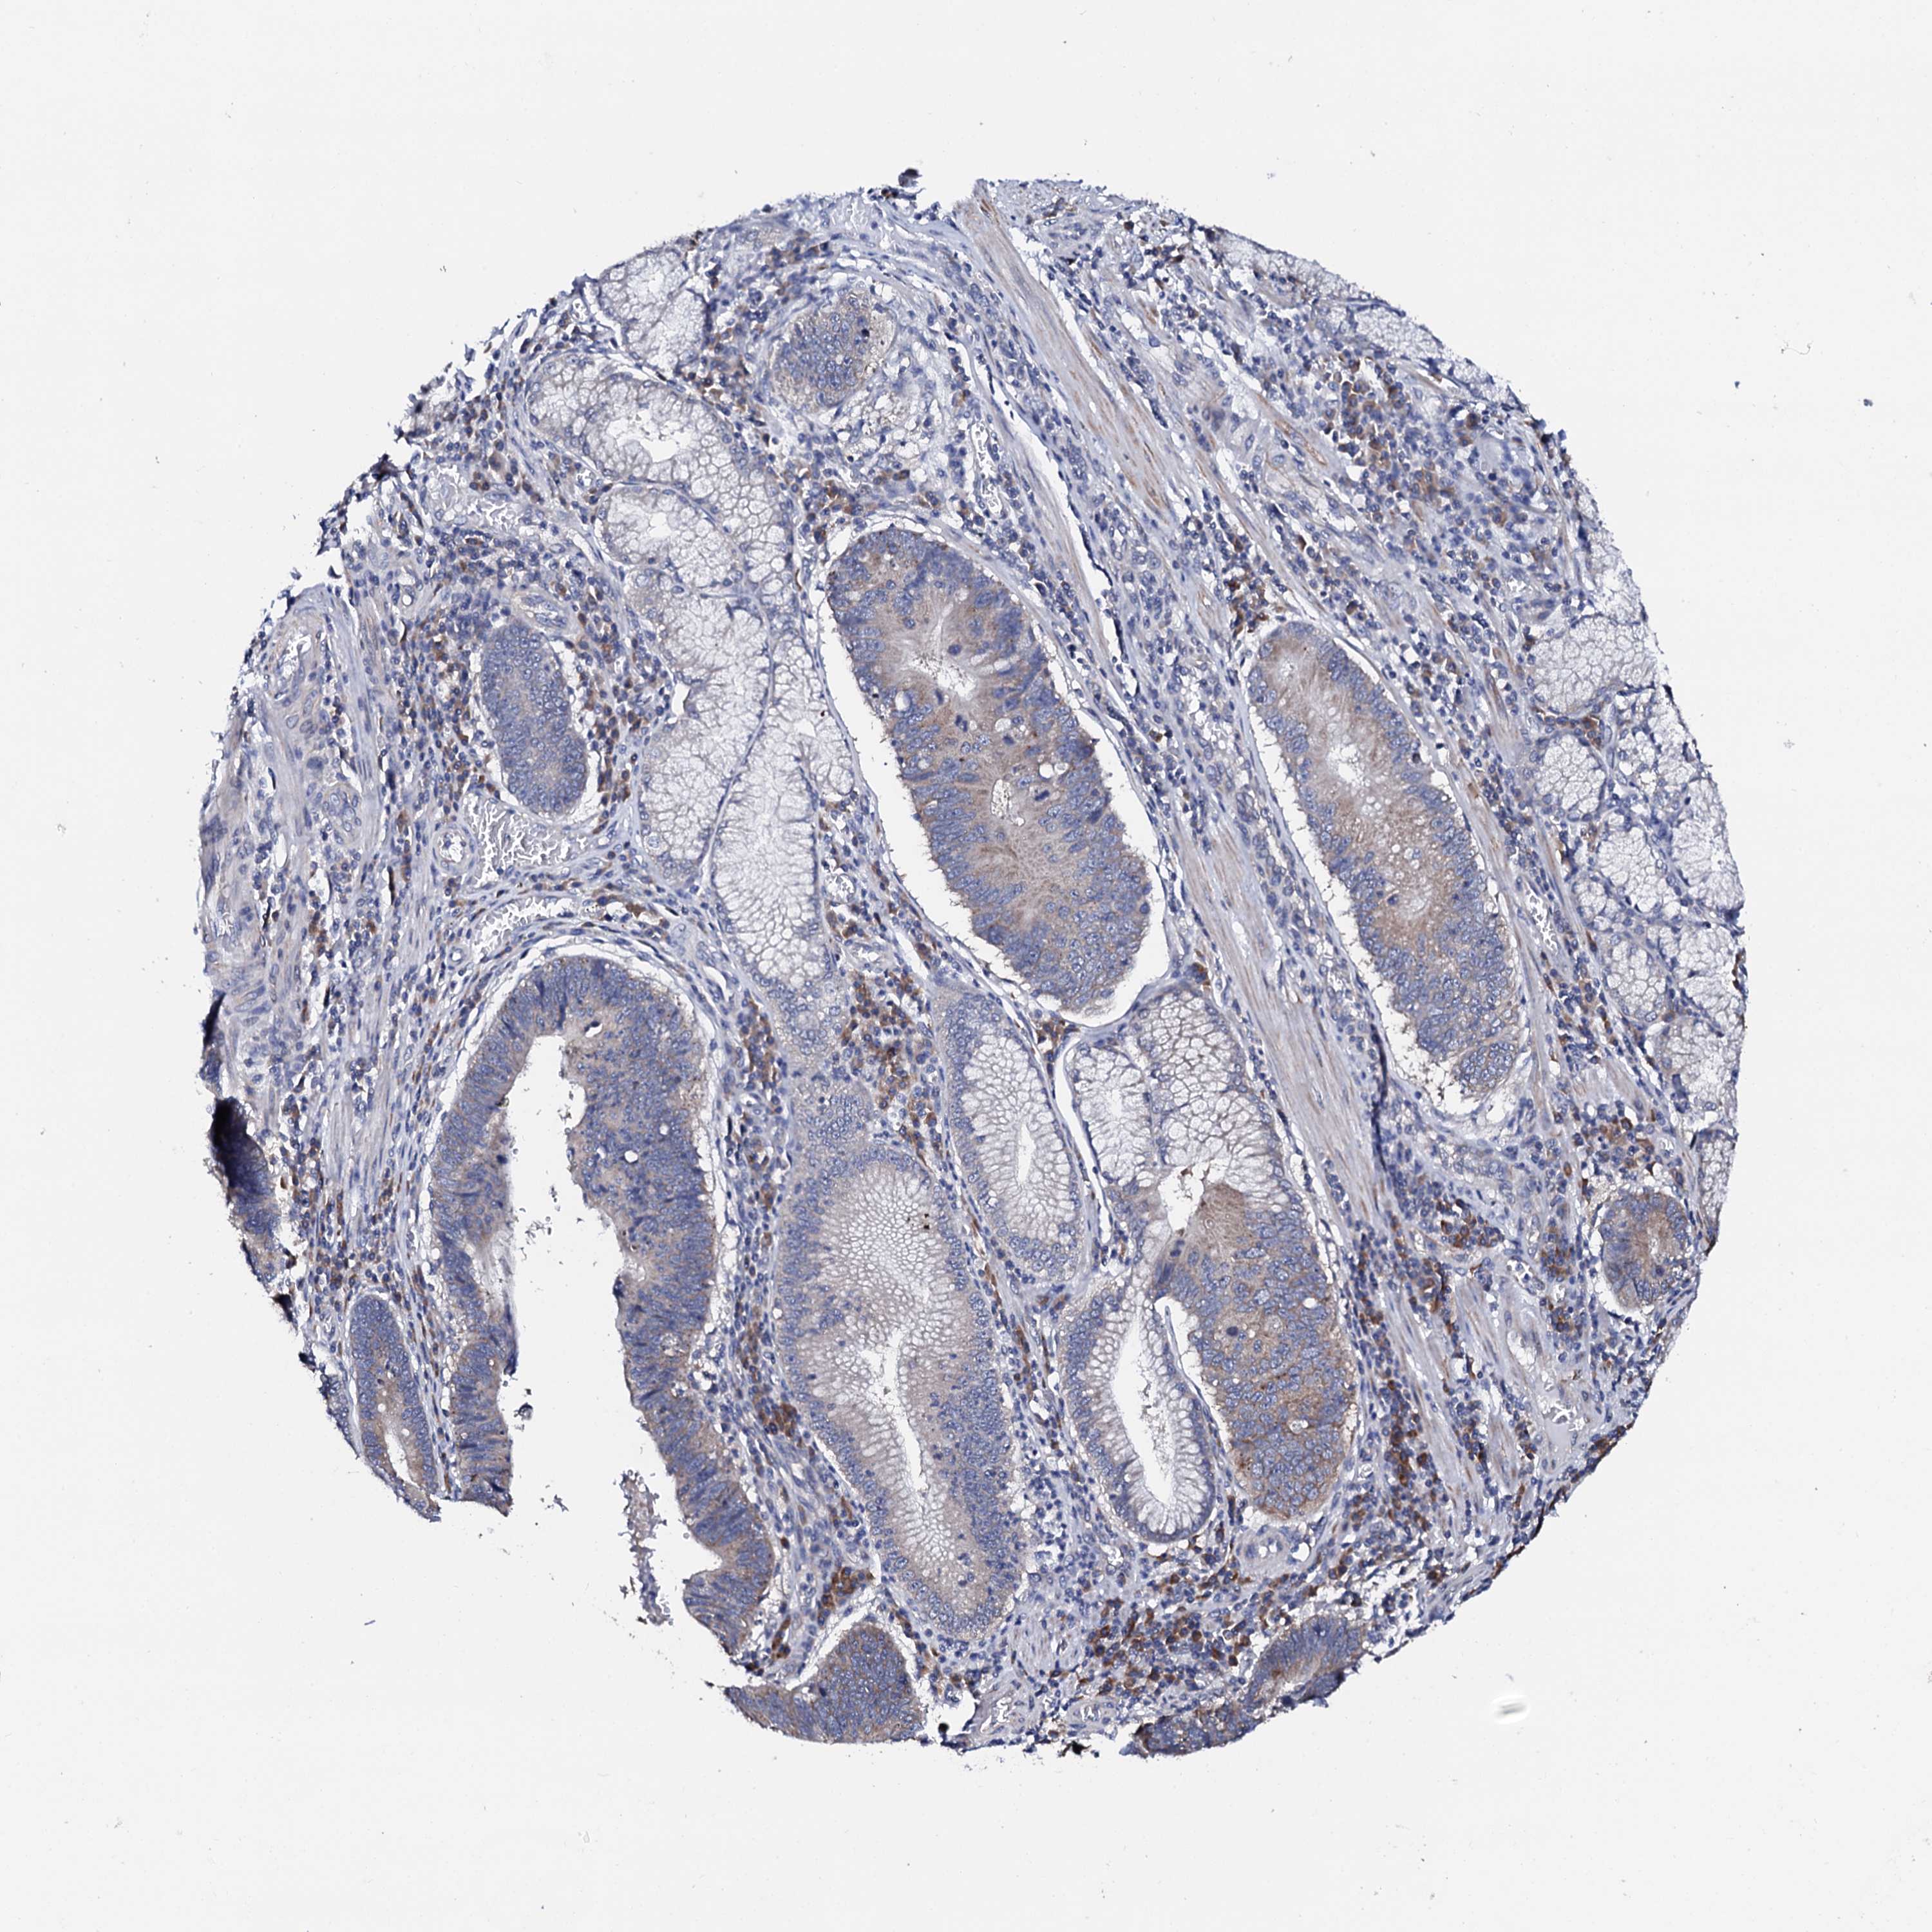

STOMACH CANCER - Protein expressioni

A mouse-over function shows sample information and annotation data. Click on an image to view it in a full screen mode. Samples can be filtered based on level of antibody staining by selecting one or several of the following categories: high, medium, low and not detected. The assay and annotation is described here.

Note that samples used for immunohistochemistry by the Human Protein Atlas do not correspond to samples in the TCGA dataset.

Antibody stainingi

Antibody staining in the annotated cell types in the current human tissue is reported as not detected, low, medium, or high, based on conventional immunohistochemistry profiling in selected tissues. This score is based on the combination of the staining intensity and fraction of stained cells.

Each image is clickable and will lead to virtual microscopy that enables deeper exploration of all samples and also displays staining intensity scores, fraction scores and subcellular localization as well as patient and tissue information for each sample.

Antibody HPA039360

Staining

High

Medium

Low

Not detected

Intensity

Strong

Moderate

Weak

Negative

Quantity

>75%

75%-25%

<25%

None

Location

Nuclear

Cytoplasmic/membranous

Cytoplasmic/membranous,nuclear

Adenocarcinoma, NOS